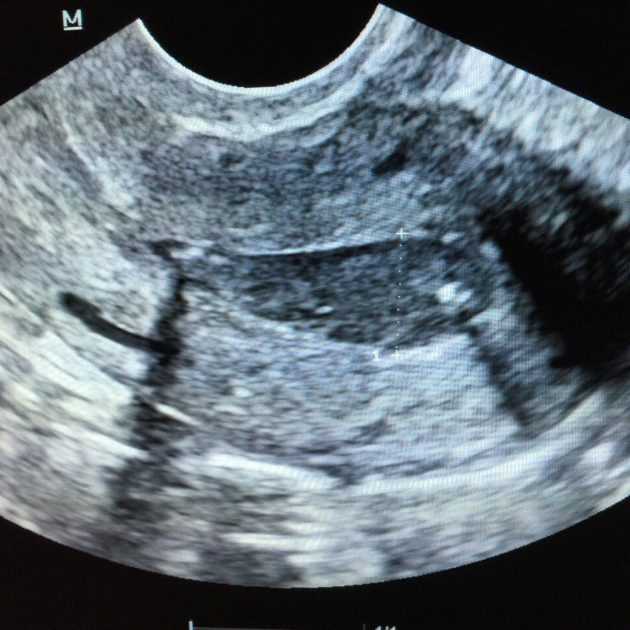

Чтобы подтвердить факт завершения процедуры, через 14 дней женщина проходит контрольное ультразвуковое исследование. Также может проводиться анализ крови на ХГЧ. Во время контрольной диагностики врач оценивает состояние половых органов и в целом организма пациентки. Риск развития осложнений после медикаментозного аборта в медицинском учреждении минимален.

представляет собой лекарственный препарат, который предназначен для проведения медикаментозного аборта на ранних сроках. Производителем этого препарата является Китай. Основным веществом этого лекарственного средства являются мифепристон. Выпускается Миропристон в форме таблеток для внутреннего применения. Рекомендованная доза таблеток составляет 600 миллиграмм. После того как пройдёт 36 часов с момента приёма препарата делается УЗИ. Вся процедура от начала приёма таблетки до проведения УЗИ должна контролироваться врачом-гинекологом. Стоимость такого препарата составляет 700 рублей.

Через 8-15 дней после применения препарата в том же лечебном учреждении следует пройти повторное обследование. При необходимости проводят УЗИ либо определяют уровень хорионического гонадотропина в сыворотке крови. При подозрении на сохранение беременности или неполный аборт нужно своевременно провести комплексное медицинское обследование. При подтверждении диагноза через 10-14 дней после приема Мизопростола необходимо провести вакуум-аспирацию с последующим гистологическим исследованием аспирата с целью оценки влияния препарата на формирование врожденных пороков развития у плода.

После выхода плода из матки кровотечение продолжается еще 5-7 дней. В этот период полностью отслаивается эндометрий. Через 2 дня после прерывания желательно сделать УЗИ. Исследование необходимо, чтобы убедиться в маточной полости не осталось частей плода, оболочек. Повторное УЗИ делают уже после полной остановки кровотечения, то есть спустя 1-2 недели. Оно необходимо для оценки результативности проведенного медикаментозного аборта и исключения развития осложнений (например, гематометры).